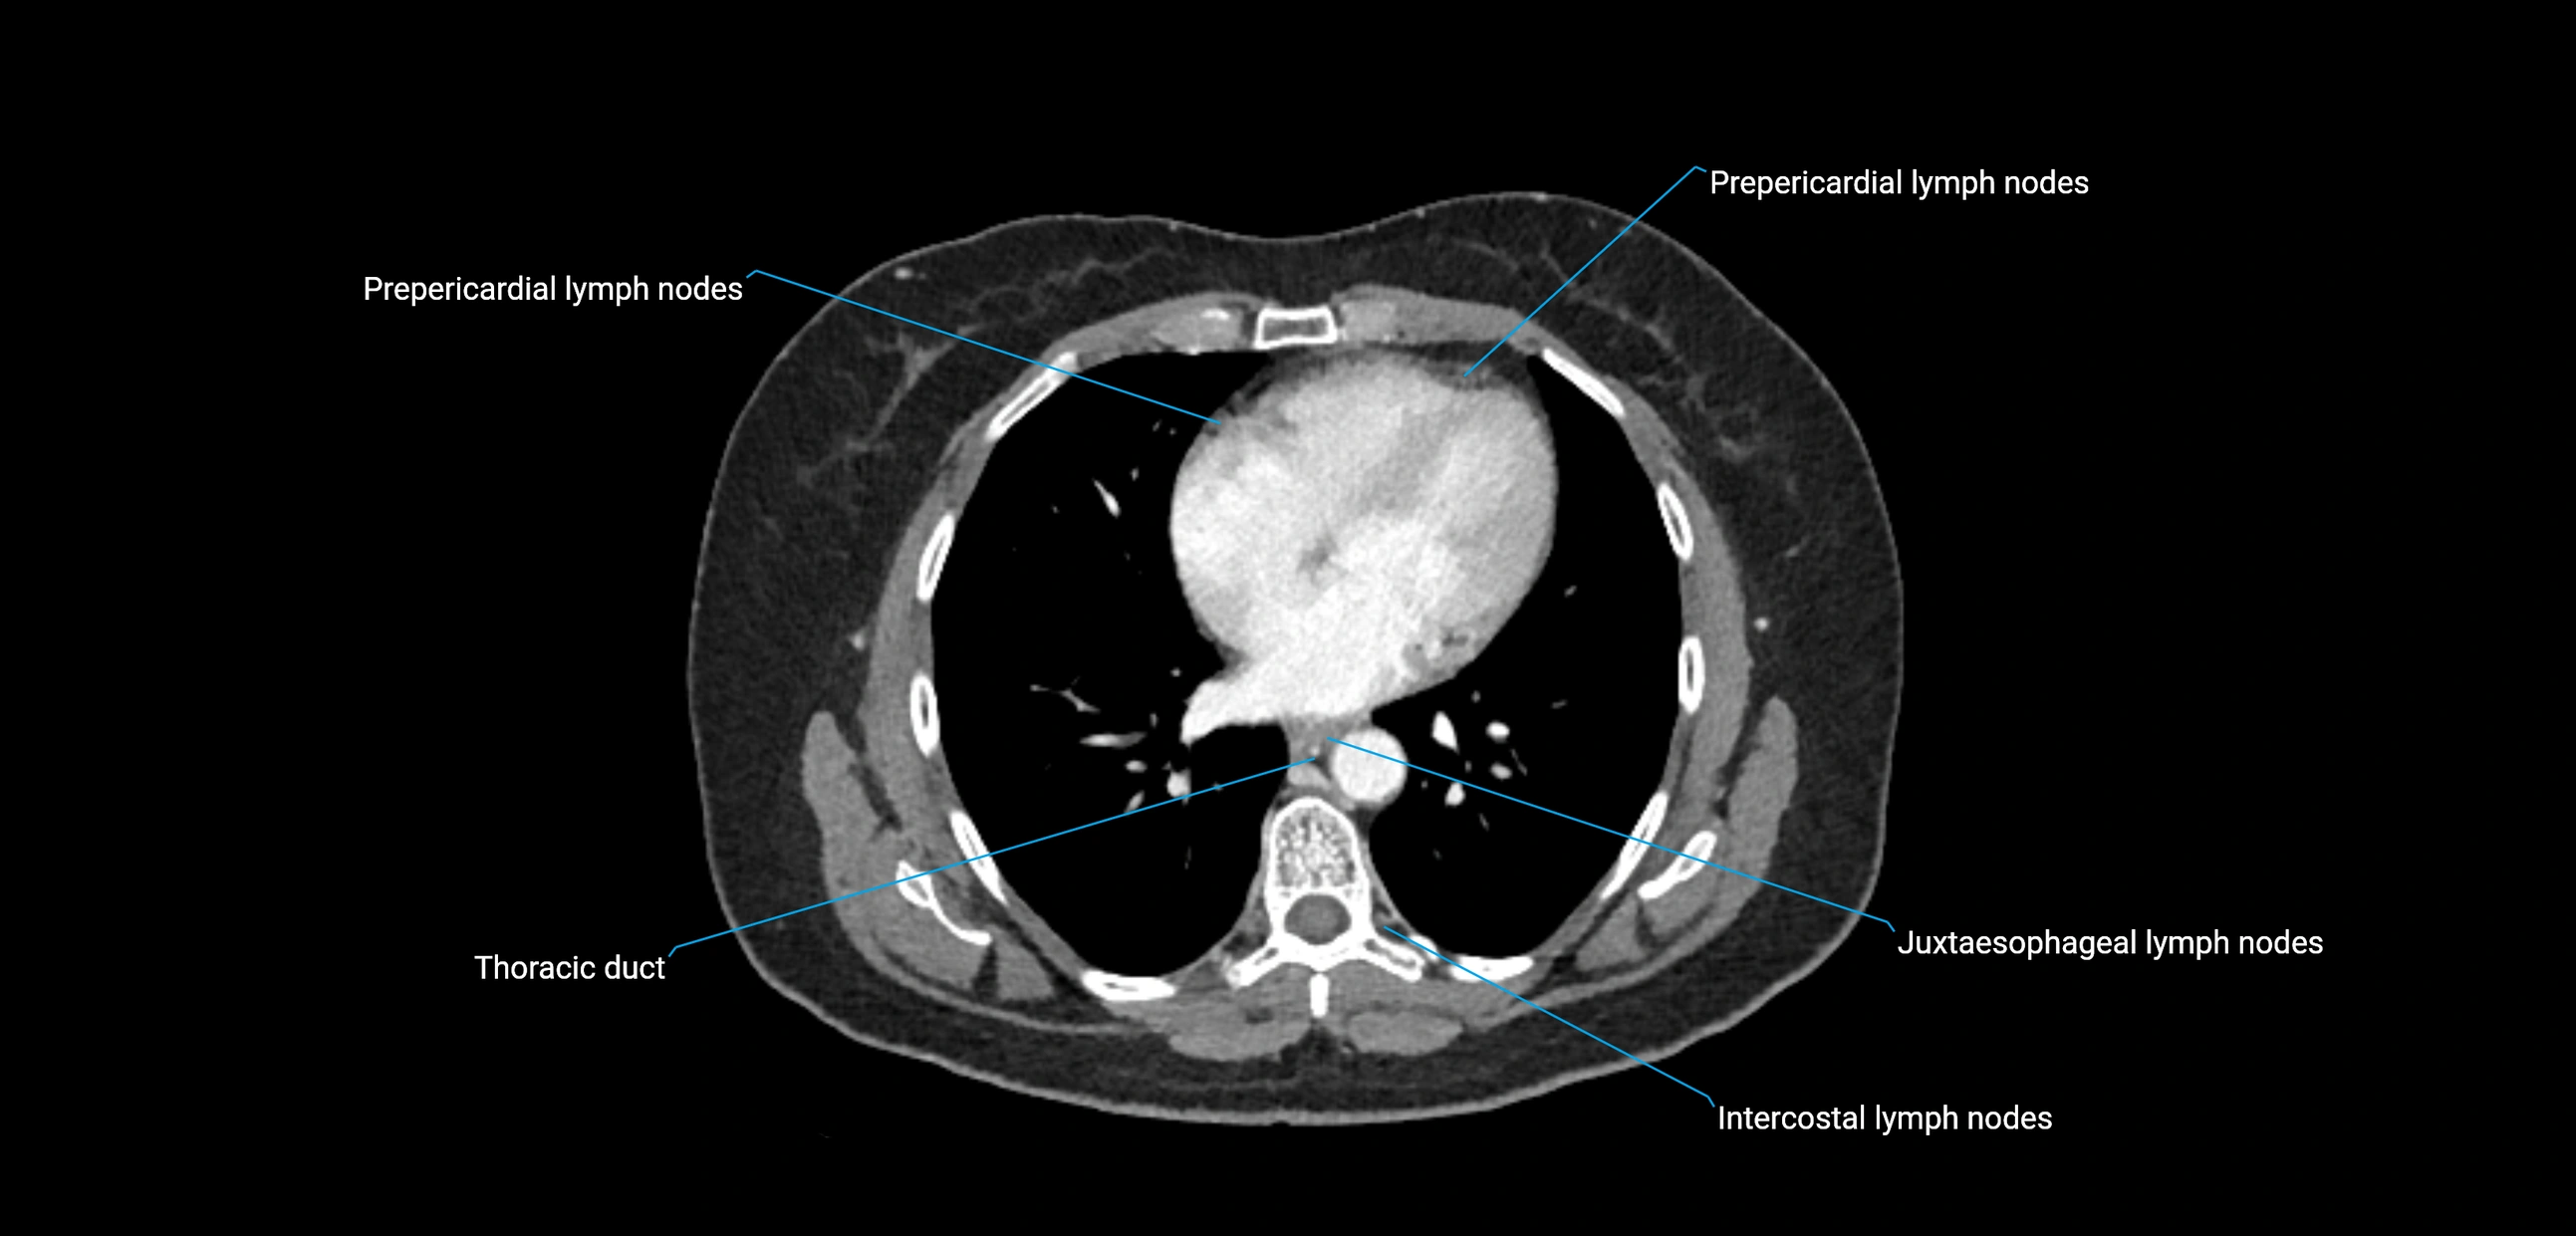

CT image

image